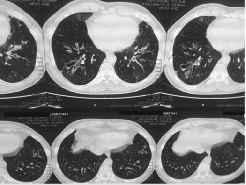

On examination he had bilateral diffuse polyphonicrhonchi. His spirometry showed very severe but reversible airflow obstruction FEV1 (0.83 L, 30% of predicted; FVC 1.3 L, 38% of predicted; FEV1/FVC 0.63). His routine blood examination was normal. He did not have peripheral eosinophilia. But his serum IgE was 573 IU/l. Specific fungal IgE was raised for Aspergillous fumigatus, Mucor racemosus, Candida Albican and dermatophagoides. CT scan of chest showed bronchiectasis in both upper and lower lobes of both lungs with mucous impaction and air fluid level in a cystic bronchiectatic cavity in right lower lobe (Figure1).

Figure 1: HRCT scan of chest showing bronchiectasis with mucous impaction and air fluid level in a cystic bronchiectatic cavity.